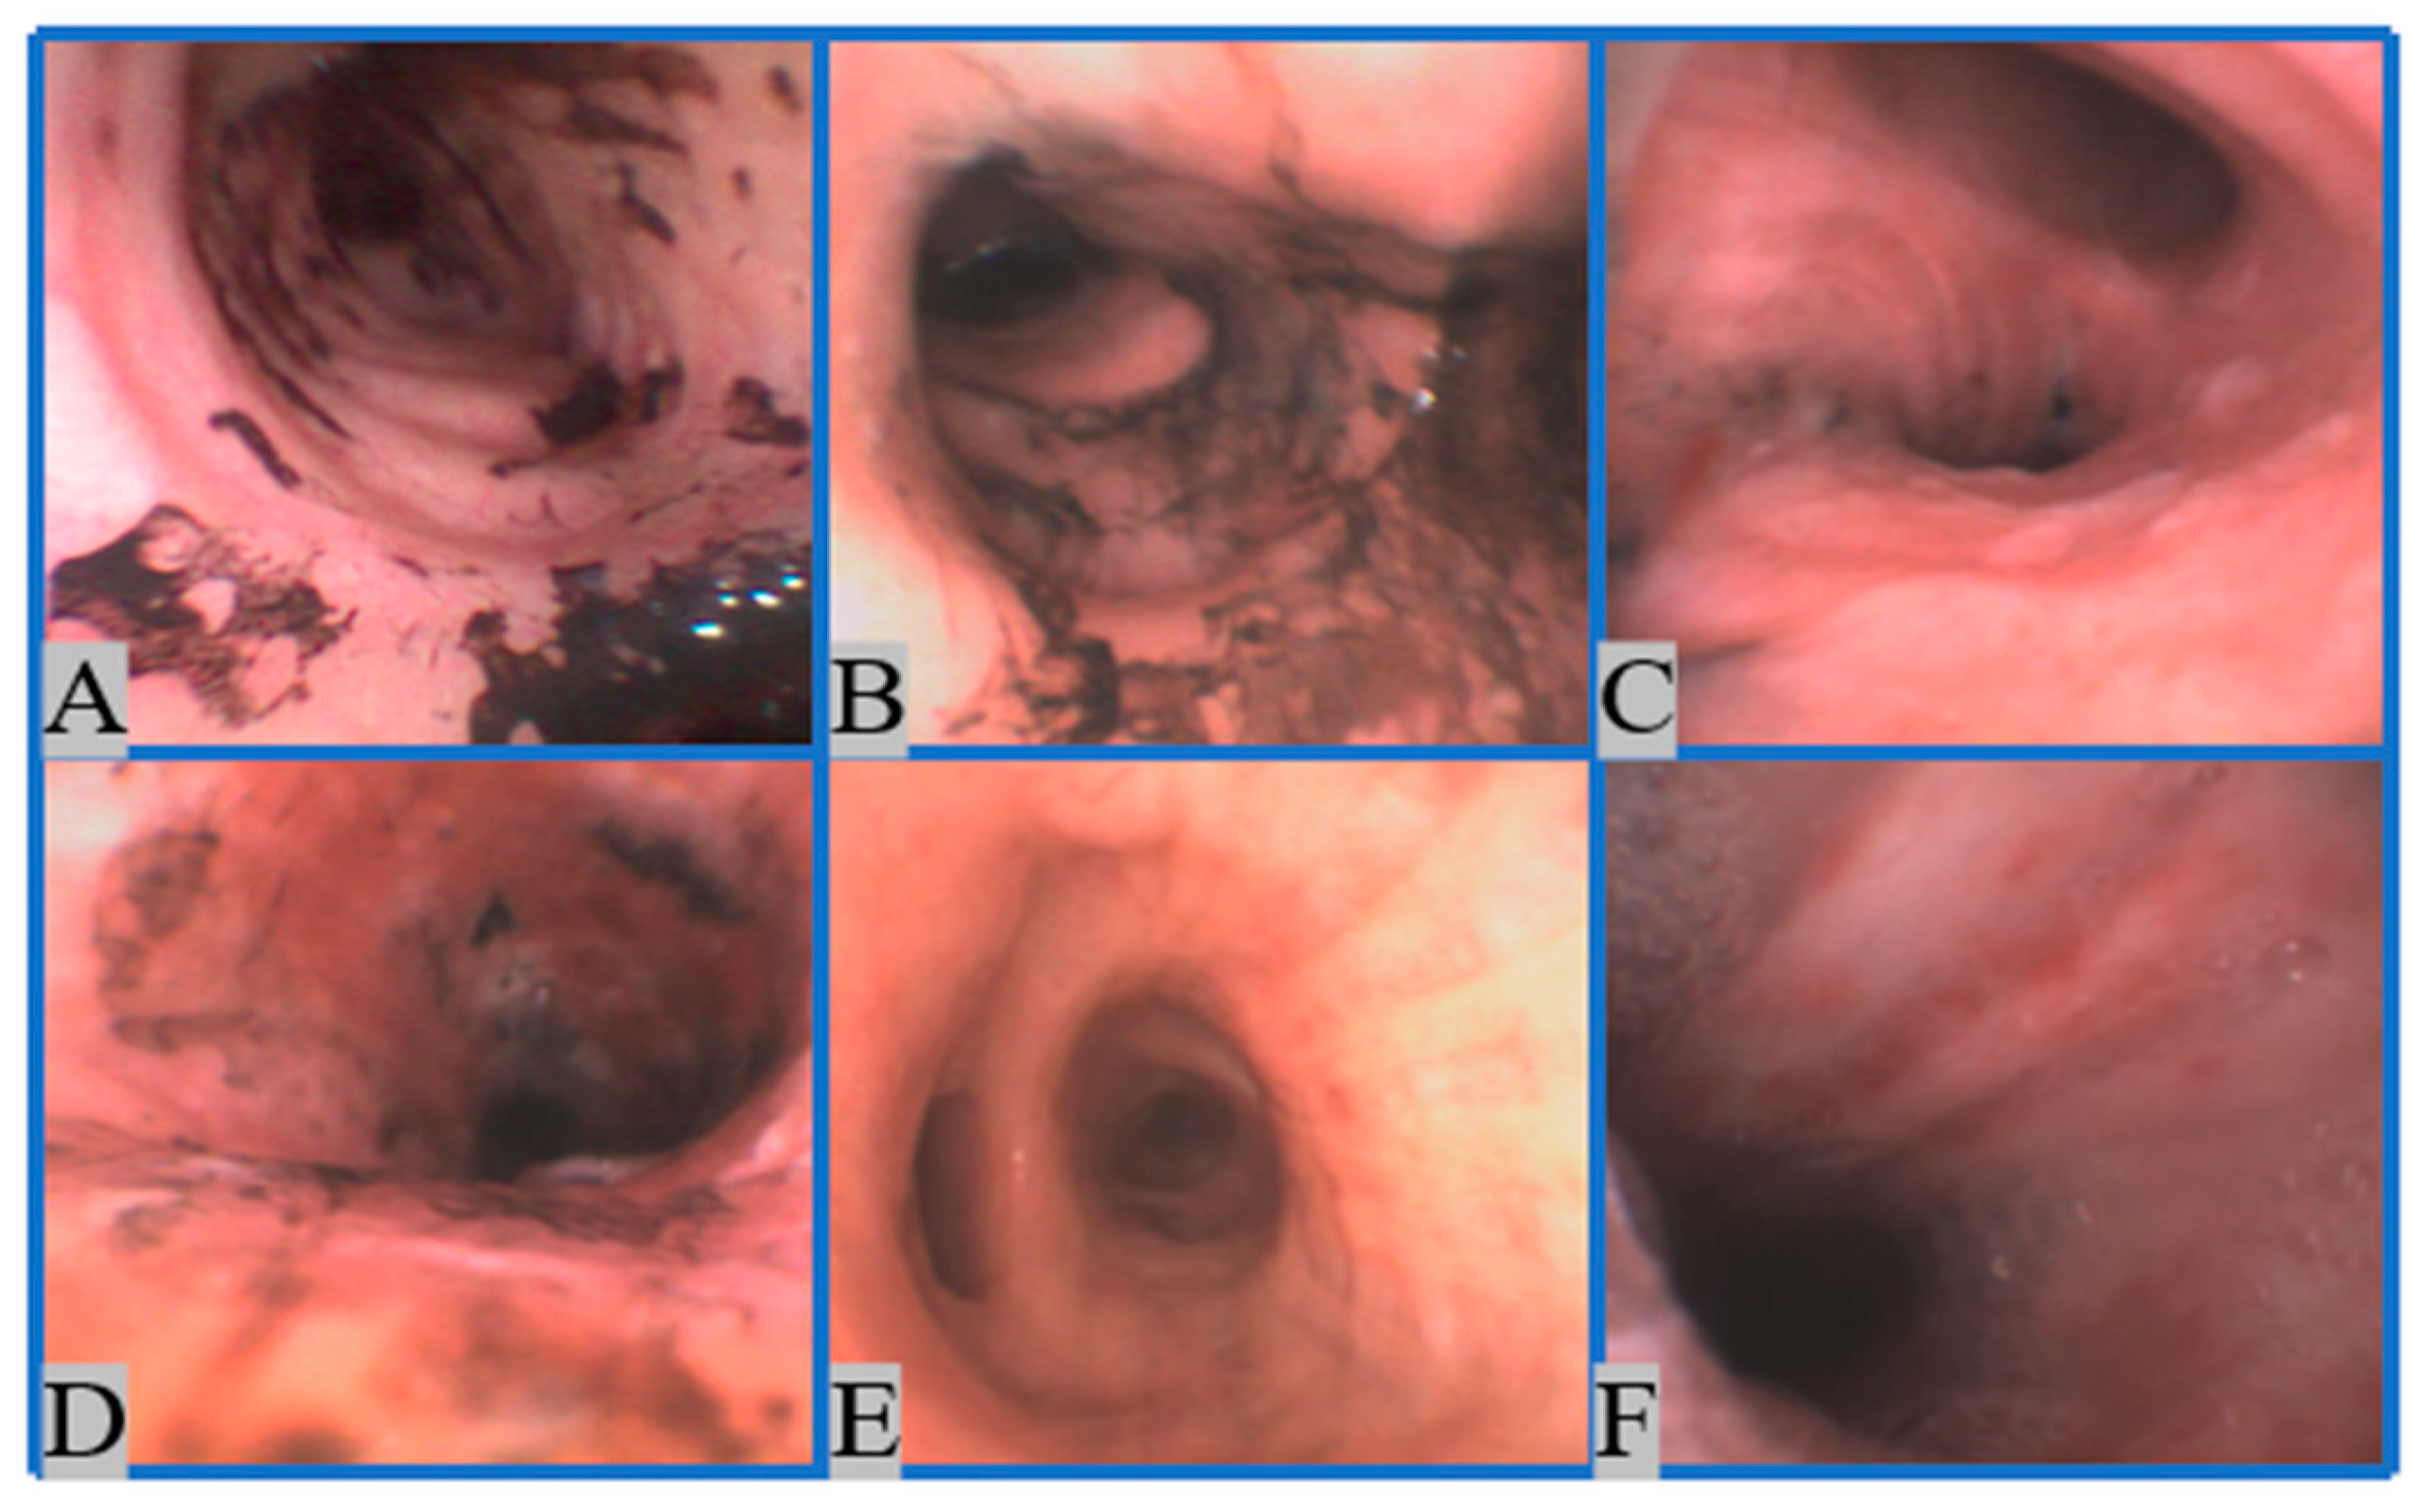

2.1.1. Image Collection